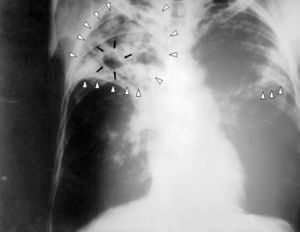

- Рентгенографии. Позволяет выявить новообразования, туберкулез на поздних стадиях (на ранних показатели еще не столь специфичны).